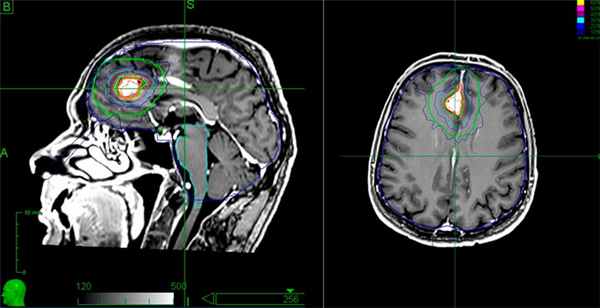

(Слева) Злокачественная менингиома, инфильтрирующая кожу волосистой части головы, череп и смежные отделы головного мозга. Протяженной вазогенный отек изображен серым цветом. Обратите внимание на остеолизис, инвазию твердой/паутинной мозговой оболочки, «грибовидную» форму опухоли и ее «вплетение» в головной мозг.

(Справа) МРТ, постконтрастное Т1 -ВИ, сагиттальный срез: злокачественная менингиома, накапливающая контрастное вещество, и вовлекающая в процесс кожу головы, череп и смежные отделы головного мозга. Обратите внимание на «грибовидное» прорастание опухоли через твердую мозговую оболочку, выраженный гипоинтенсивный отек мозговой ткани. (Слева) МРТ, Т2-ВИ, аксиальный срез: у мужчины 71 года визуализируется объемное образование с четкими контурами, прилежащее широким основанием к твердой мозговой оболочке по ходу большого крыла клиновидной кости. Объемное образование изоинтенсивно по отношению к коре, отчетливо визуализируется ликворная щель, признаков локальной инвазии мозгвой ткани не отмечается.

(Справа) МРТ, постконтрастное Т1-ВИ, режим подавления сигнала от жира, аксиальный срез: интенсивное равномерное контрастное усиление. При операции признаков инвазии смежной мозговой паренхимы выявлено не было. При патоморфологическом исследовании была диагностирована менингиома grade II.

- лучевая терапия на установке Кибер-Нож — современный и малотравматичный метод лечения образований размером до 3.5-4 см. На опухоль воздействуют направленным потоком ионизирующего излучения. Окружающие ткани при этом практически не повреждаются.

Лечение менингиомы. Этапы подготовки мишени для облучения на системе "Кибер-нож”

Кибер-Нож позволяет удалить опухоль без боли и повреждения важных структур мозга. Процедура проводится в амбулаторных условиях без госпитализации пациента, после терапии пациент сразу может ехать домой. В ПЭТ-центре план лечения составляется врачами радиологом и онкологом, что позволяет выбрать наиболее эффективную тактику для конкретного пациента.